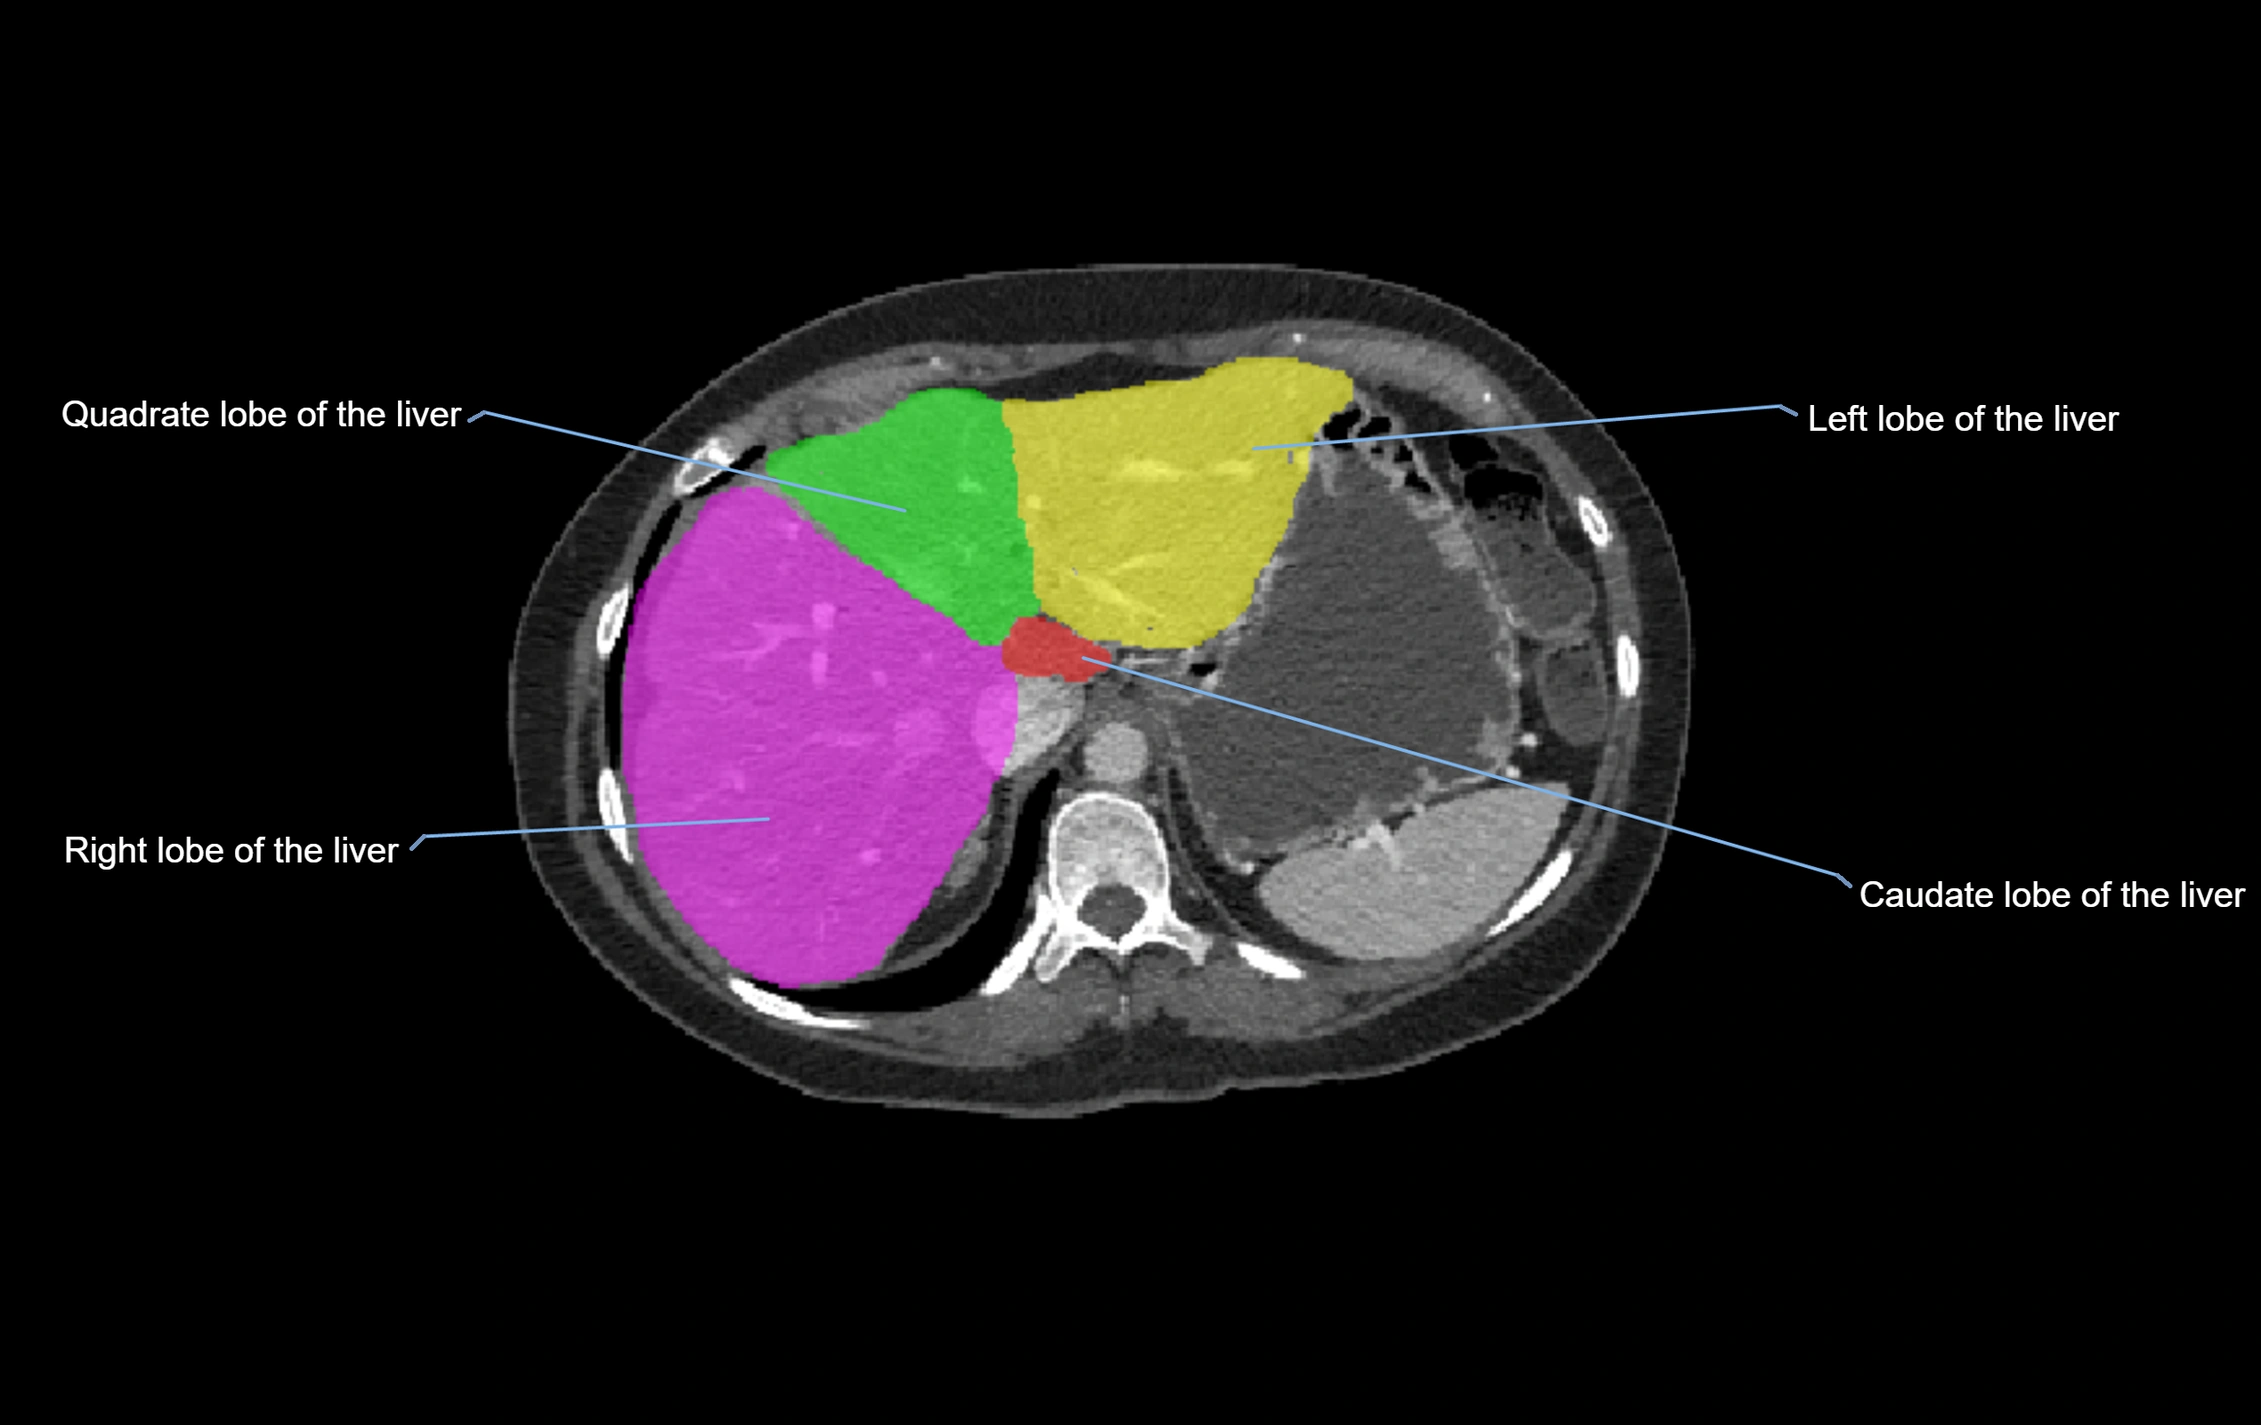

The caudate lobe of the liver is a distinct anatomical subdivision of the liver, designated as segment I in Couinaud’s classification. It lies on the posterior surface of the liver, between the fissure for the ligamentum venosum (left boundary) and the groove for the inferior vena cava (IVC) (right boundary). Superiorly, it is related to the posterior liver surface, and inferiorly it is separated from the left lobe by the porta hepatis.

The caudate lobe is unique because it receives dual portal venous and arterial inflow from both the right and left portal veins and hepatic arteries. It also has independent venous drainage directly into the IVC via multiple small hepatic veins, unlike other lobes that drain through the three main hepatic veins.

This anatomical autonomy makes the caudate lobe especially significant in liver surgery, transplantation, and hepatic venous outflow obstruction syndromes (e.g., Budd–Chiari syndrome). Enlargement of the caudate lobe is a characteristic imaging feature in chronic liver disease and cirrhosis.